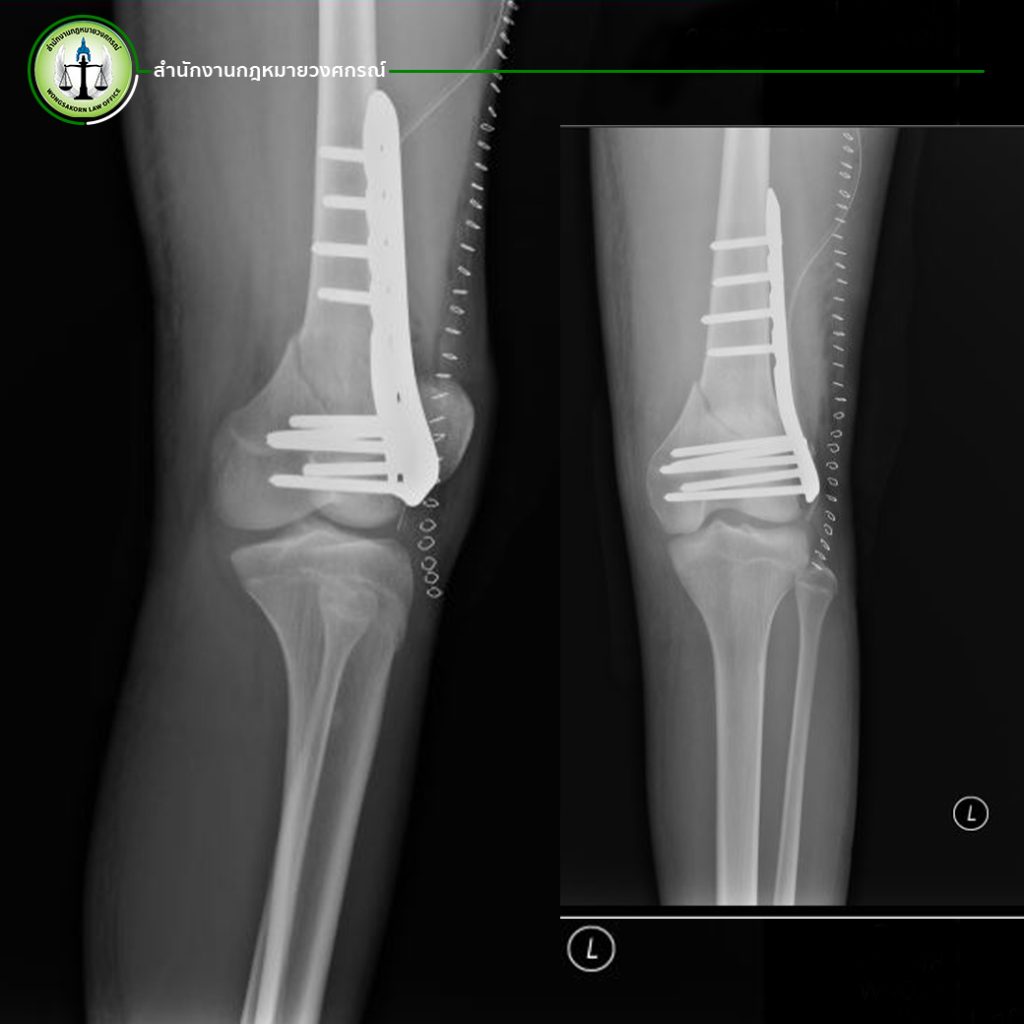

เหตุการณ์ครั้งนี้เกิดจากผู้เสียหายได้ขับขี่รถยนต์แล้วเกิดการเฉี่ยวชนกับรถเก๋งคันหนึ่ง แต่รถยนต์ที่ผู้บาดเจ็บขับขี่นั้นถูกชนท้ายโดยรถยนต์อีกคันหนึ่ง เป็นเหตุทำให้รถของผู้บาดเจ็บที่มีการทำประกันภัยเอาไว้กับบริษัทประกันภัยเกิดความเสียหาย มีผู้โดยสารได้รับบาดเจ็บ 2 คน โดยผู้บาดเจ็บที่ 1 ได้รับบาดเจ็บสาหัส กระดูกต้นคอหัก และกระดูกไหล่ขวาหัก จนต้องเข้ารับการผ่าตัดดามเหล็กไว้ที่หัวไหล่ และต้องพักรักษาตัวเป็นเวลา 3 เดือน หลังผ่าตัดเอาเหล็กออกยังต้องเข้าทำกายภาพบำบัด ปัจจุบันผู้บาดเจ็บยังต้องรักษาอาการบาดเจ็บอย่างต่อเนื่องและมีอาการบาดเจ็บรบกวนอยู่ตลอดเวลา เป็นอุปสรรคต่อการใช้ชีวิตอย่างมาก

ทั้งนี้ผู้บาดเจ็บได้สำรองจ่ายค่ารักษาอันจำเป็นไปแล้วกว่า 200,000 บาท ยังไม่รวมถึงค่าขาดประโยชน์จากรายได้ต่อเดือนอีก 150,000 บาท จากการที่ผู้บาดเจ็บดำรงอยู่ในตำแหน่งผู้บริหารระดับสูงของบริษัทของบริษัท การได้รับบาดเจ็บสาหัสจากในครั้งนี้ต้องรักษาตัวเป็นเวลานาน ทำให้สูญเสียรายได้เป็นจำนวนมากและส่งผลกระทบต่อการบริหารบริษัท ผู้บาดเจ็บต้องทำการผ่าตัดดามเหล็กเอาไว้ที่ไหล่ขวา และต้องผ่าตัดเพื่อเอาเหล็กออก ทำให้ต้องมีค่าใช้จ่ายในการผ่าตัด รวมค่ารักษาพยาบาลหลังการผ่าตัดเป็นจำนวนเงินกว่า 80,000 บาท ซึ่งราคานี้เป็นค่าใช้จ่ายที่แพทย์ได้ประเมินการรักษาในเบื้องต้น ยังไม่รวมหากเกิดอาการแทรกซ้อนอื่นๆ ขณะทำการรักษา รวมถึงค่าเวชภัณฑ์อื่นๆ

ระหว่างที่ผู้บาดเจ็บต้องรักษาตัวอยู่ในประเทศไทย ผู้บาดเจ็บต้องเดินทางไปมาระหว่างบ้านกับโรงพยาบาลอยู่บ่อยครั้ง ทำให้มีค่าใช้จ่ายระหว่างที่ต้องรักษาตัว แต่ว่าอาการบาดเจ็บที่หัวไหล่ไม่ดีขึ้น กระดูกบริเวณหัวไหล่ที่หักไม่เชื่อมติดกัน ผู้บาดเจ็บจึงต้องทำการบินไปรักษาตัวที่ประเทศไต้หวัน และต้องเข้ารับการผ่าตัดอีกครั้ง ทำให้มีค่าใช้จ่ายในการผ่าตัดอีกเป็นจำนวนเงิน 158,080 ดอลลาร์ไต้หวัน คิดเป็นเงินไทย 161,241 บาท อีกทั้งยังต้องเสียค่าเครื่องบินเพื่อบินไปรักษาเป็นจำนวนเงิน 14,300 บาท และหลังจากผ่าตัดผู้บาดเจ็บยังต้องเข้าทำกายภาพบำบัดอย่างต่อเนื่อง ซึ่งเป็นการรักษาที่กินระยะเวลานาน และเสียค่าใช้จ่ายเป็นจำนวนมาก ซึ่งความจริงแล้วค่าใช้จ่ายในส่วนนี้ผู้บาดเจ็บสามารถเรียกร้องได้กับบริษัทประกันภัย แม้ว่าผู้บาดเจ็บจะเดินทางไปรักษาตัวที่ต่างประเทศก็ตาม